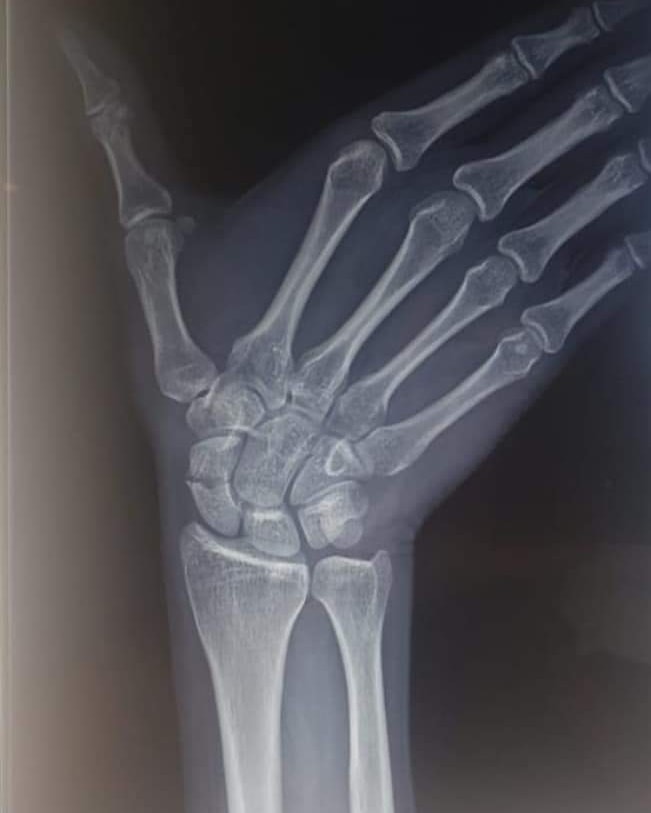

El Dr. Javier Severiche nuevamente dando soluciones a personas que requieren de su gran experiencia, en Clinica Trauma Clinic este sábado entró a cirugía para solucionar una fractura en la muñeca derecha de un paciente de 25 años.

Presenta una fractura de escafoides. Se realiza una osteosintesis con mini incision utilizando un tornillo de Herbert,logró una buena estabilización con buenos resultados.